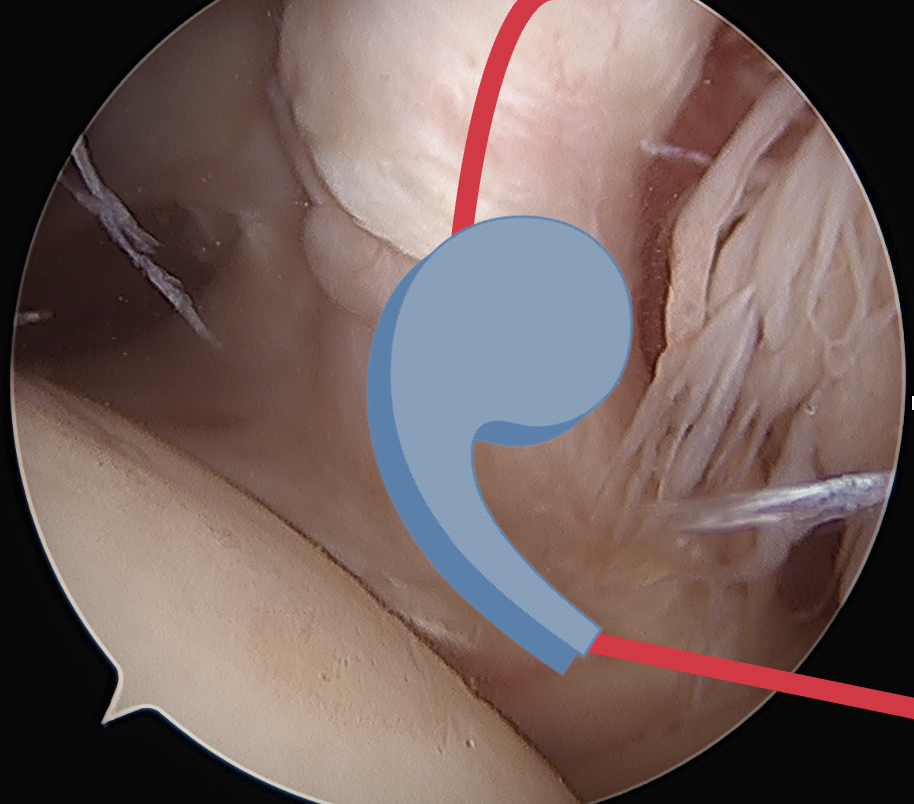

Medially dislocated biceps tendon with upper border subscapularis tear

Full thickness tear of subscapularis off insertion revealed with grasper